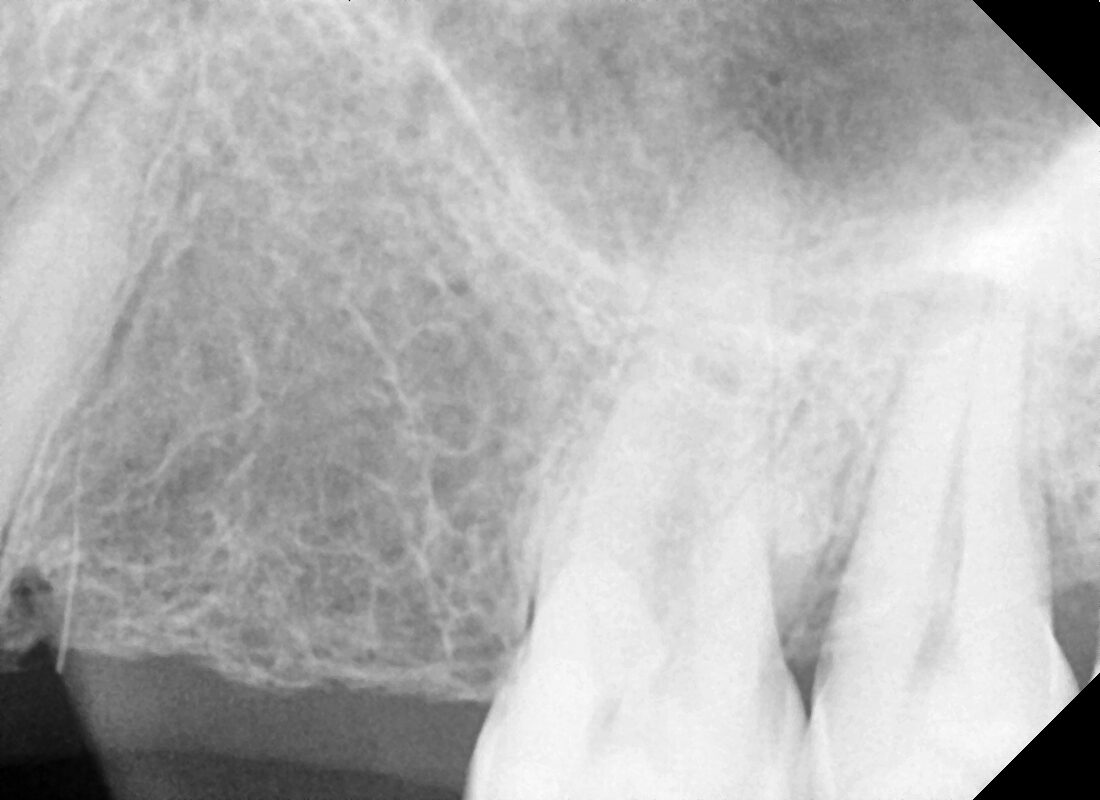

Prices are dynamic and starts from 12000 onwards… In this we have placed two Dentium implant which cost the patient 15000/implant Reply

Prices are dynamic and starts from 12000 onwards… In this we have placed two Dentium implant which cost the patient 15000/implant